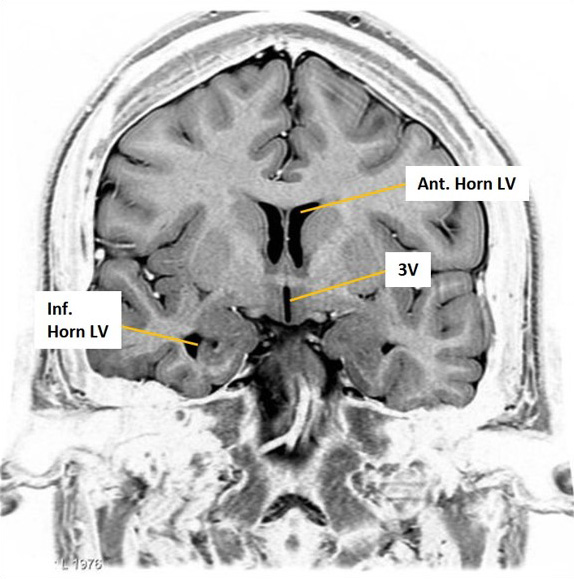

The shape of lateral ventricles changes from anterior to posterior

- Portions of the lateral ventricle include: the anterior horn, body, atrium, posterior horn, and inferior horn

- Septum pellucidum: The midline membrane separating the two lateral ventricles

- Interventricular foramen (foramen of Monro) opening into the 3V from the LV